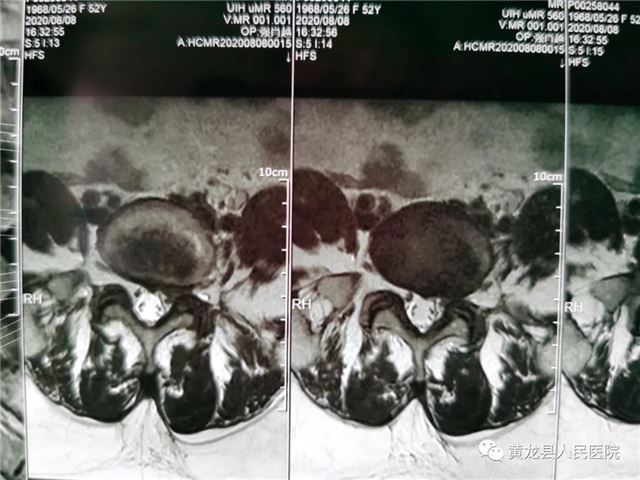

张某,女,52岁,近1月来,出现腰部疼痛,反复发作,并向左侧下肢放射,劳累后加重,休息后减轻,无法正常行走,严重影响生活质量,在家人陪同下来到黄龙县人民医院外科就诊。恰逢唐都医院骨科帮扶支援专家高全有副主任医师门诊坐诊,首诊详细了解患者病史,经仔细查体,结合影像学检查,最终诊断为:腰椎间盘突出症(L5-S1)。

术前腰椎MRI